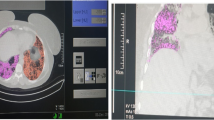

Experimental study

Within the experimental study, 80 HRCT datasets of four immunosuppressant-naive patients (4 patients x 10-fold measurement without and with operator adjustment) with different IRD-ILD were analysed using AI-based quantification with the SATORI platform (AI-based quantification of pulmonary HRCT; AIqpHRCT]) (see study protocol in Fig. 1; Table 1; Fig. 2). These four patients were randomly selected from clinical routine for typical HRCT patterns. All HRCT were performed as part of organ screening for lung involvement for clinical routine and not for study purposes.

We evaluated the following CV values in respect of GGO ranged between CV = 9.25% (right lower lobe) and CV = 47.10% (left upper lobe) with an ICC = 0.998 (95%CI 0.996-1.000) (Fig. 2C).

Non-specific interstitial pneumonia (NSIP)

Concerning GGO as a component of NSIP, the CV ranged from 4.92% (left lower lobe) to 25.54% (right upper lobe) with an ICC = 0.998 (95%CI 0.993-1.000). Lower CV values were presented for the reticulation component ranging between 1.02% (right lower lobe) and 12.48% (right middle lobe) with an ICC = 1.000 (95%CI 1.000–1.000) (Fig. 2A and B).

Usual interstitial pneumonia (UIP)

The CV values for GGO as a component of UIP ranged from 3.12% (right lower lobe) to 10.50% (right upper lobe) with an ICC = 1.000 (95%CI 0.999-1.000). For reticulation, CV values ranged from 0.001% (right upper lobe) to 15.89% (right middle lobe) with an ICC = 0.999 (95%CI 0.997-1.000). Regarding honeycombing, a CV between 4.20% (left lower lobe) and 26.91% (right middle lobe), with an ICC = 0.997 (95%CI 0.992–0.999) was observed (Fig. 2D).

Granuloma/proliferation

For granuloma/proliferation the CV ranged between 0.001% (left lower lobe) to 28.75% (left upper lobe) with an ICC = 0.999 (95%CI 0.999-1.000) (Fig. 1).